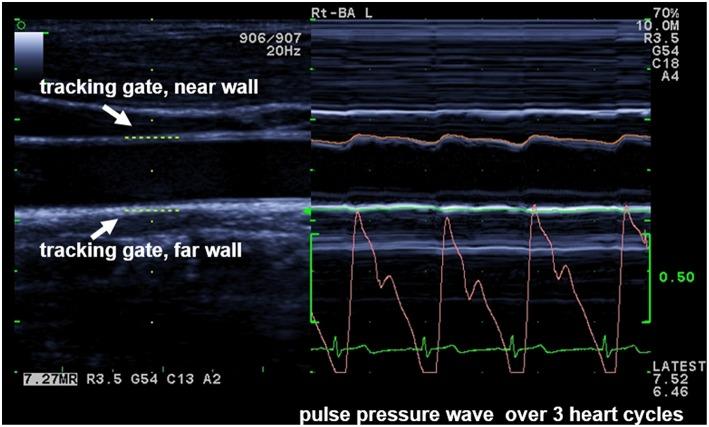

Vascular alterations may lead to manifest cardiovascular disease in future life. There is a tremendous time delay between the onset and obvious clinical appearance of vascular alterations. Pulse wave velocity (PWV) is one subclinical parameter to detect vascular alterations at a very early stage. Different techniques exist to measure PWV non-invasively as a vascular parameter-all with their own technique-inherent advantages, challenges, and pitfalls. The aim of this study was to compare two techniques to measure PWV, to assess their agreement, and interchangeability. In 780 (♀ = 49.4%) healthy children and adolescents (mean age: 11.61 ± 2.11 years), PWV was obtained with two different techniques. Ultrasound-measured local PWV (PWVβ) at the carotid artery was graphically compared by a Bland-Altman plot with aortic PWV (aPWV), measured oscillometrically on the brachial artery. Reproducibility was assessed with the concordance correlation coefficient by Lin (ρc). Furthermore, participants were categorized by BMI as normal weight (N) or overweight/obese (O) to identify differences in PWVβ and aPWV caused by an increased BMI. Mean PWVβ was lower (4.01 ± 0.44 m/s) than mean aPWV (4.67 ± 0.34 m/s). The two methods differ by mean Δ0.66 ± 0.47 m/s (95% CI: 0.62 to 0.69 m/s; < 0.001). Bland-Altman analysis indicated the 95% limits of agreement (-0.26 to 1.57) without any evidence of systemic difference. Lin's ρc represented a weak concordance between PWVβ and aPWV (ρc = 0.122; 95% CI: 0.093-0.150). There was no difference in PWVβ between N and O, whereas aPWV was higher in O: 4.81 ± 0.42 m/s than in N: 4.65 ± 0.32 m/s ( < 0.001). The difference, Δ0.16 m/s, 95% CI [-0.25; -0.08], was significant, = -3.76, < 0.001, with a medium-sized effect. PWVβ (ultrasound) and aPWV (oscillometry) show a level of disagreement that includes clinically important discrepancies. A discrimination between normal and altered vascular function was possible with aPWV but not with PWVβ.

血管改变可能会在未来导致明显的心血管疾病。从血管改变开始到出现明显的临床症状之间存在很长的时间延迟。脉搏波速度(PWV)是在非常早期阶段检测血管改变的一个亚临床参数。存在不同的技术以非侵入方式测量PWV作为血管参数——所有这些技术都有其自身技术固有的优点、挑战和缺陷。本研究的目的是比较两种测量PWV的技术,评估它们的一致性和互换性。在780名(女性占49.4%)健康儿童和青少年(平均年龄:11.61±2.11岁)中,用两种不同技术获得PWV。通过Bland - Altman图将超声测量的颈动脉局部PWV(PWVβ)与通过肱动脉示波法测量的主动脉PWV(aPWV)进行图形比较。用Lin的一致性相关系数(ρc)评估可重复性。此外,根据BMI将参与者分为正常体重(N)或超重/肥胖(O)组,以确定BMI增加导致的PWVβ和aPWV的差异。平均PWVβ(4.01±0.44米/秒)低于平均aPWV(4.67±0.34米/秒)。两种方法的平均差异为0.66±0.47米/秒(95%CI:0.62至0.69米/秒;P<0.001)。Bland - Altman分析表明一致性界限为95%(-0.26至1.57),没有任何系统性差异的证据。Lin的ρc表明PWVβ和aPWV之间存在弱一致性(ρc = 0.122;95%CI:0.093 - 0.150)。N组和O组之间的PWVβ没有差异,而O组的aPWV(4.81±0.42米/秒)高于N组的aPWV(4.65±0.32米/秒)(P<0.001)。差异为0.16米/秒,95%CI[-0.25;-0.08],具有统计学意义,t = -3.76,P<0.001,效应量为中等。PWVβ(超声)和aPWV(示波法)显示出一定程度的不一致,包括临床上重要的差异。使用aPWV可以区分正常和改变的血管功能,但使用PWVβ则不行。